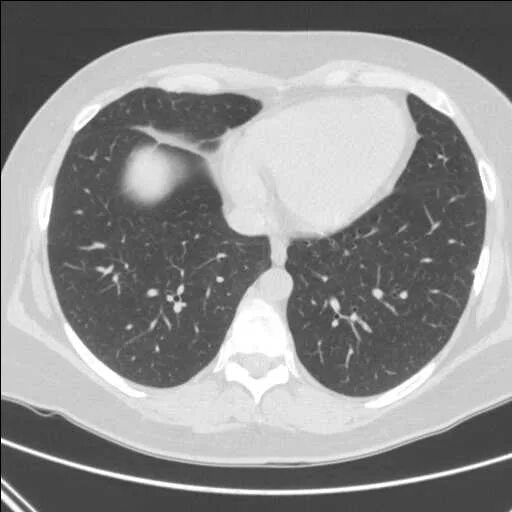

Кт после ковид